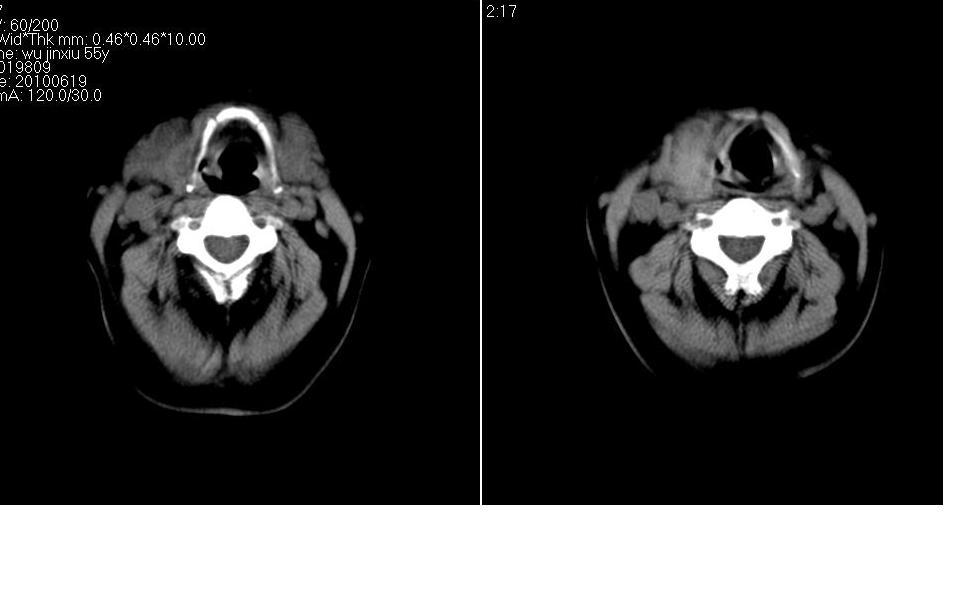

女 55岁 右侧颈部包块十年余,自己感觉有增大。

来源于右侧甲状腺  边界清晰,内可见点状钙化,向下生长达前上纵隔血管间隙内  考虑甲状腺腺瘤并胸内甲状腺肿